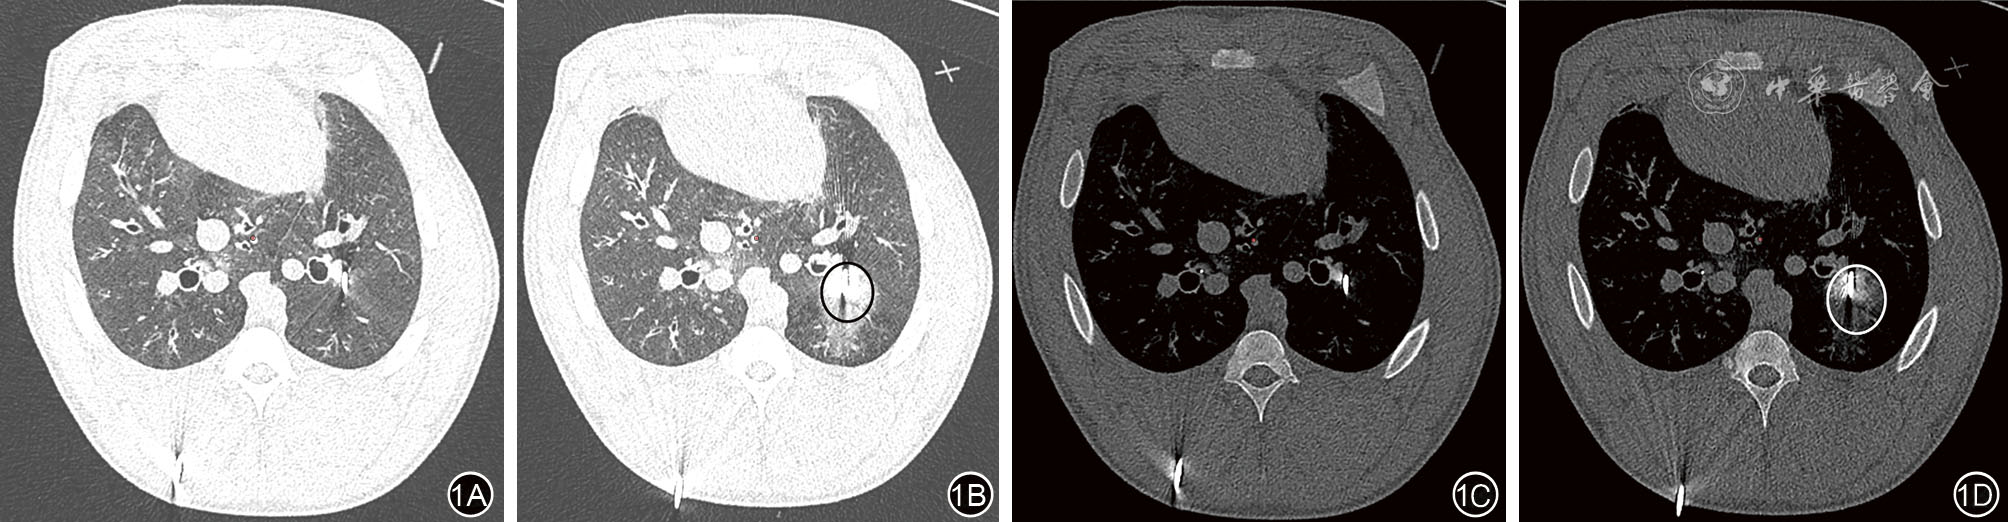

图1 100 W 8 min活体猪肺微波消融术中CT图 1A、1B:微波消融前后的肺窗,黑圈为消融范围;1C、1D:微波消融前后的纵隔窗,白圈所示为消融范围。